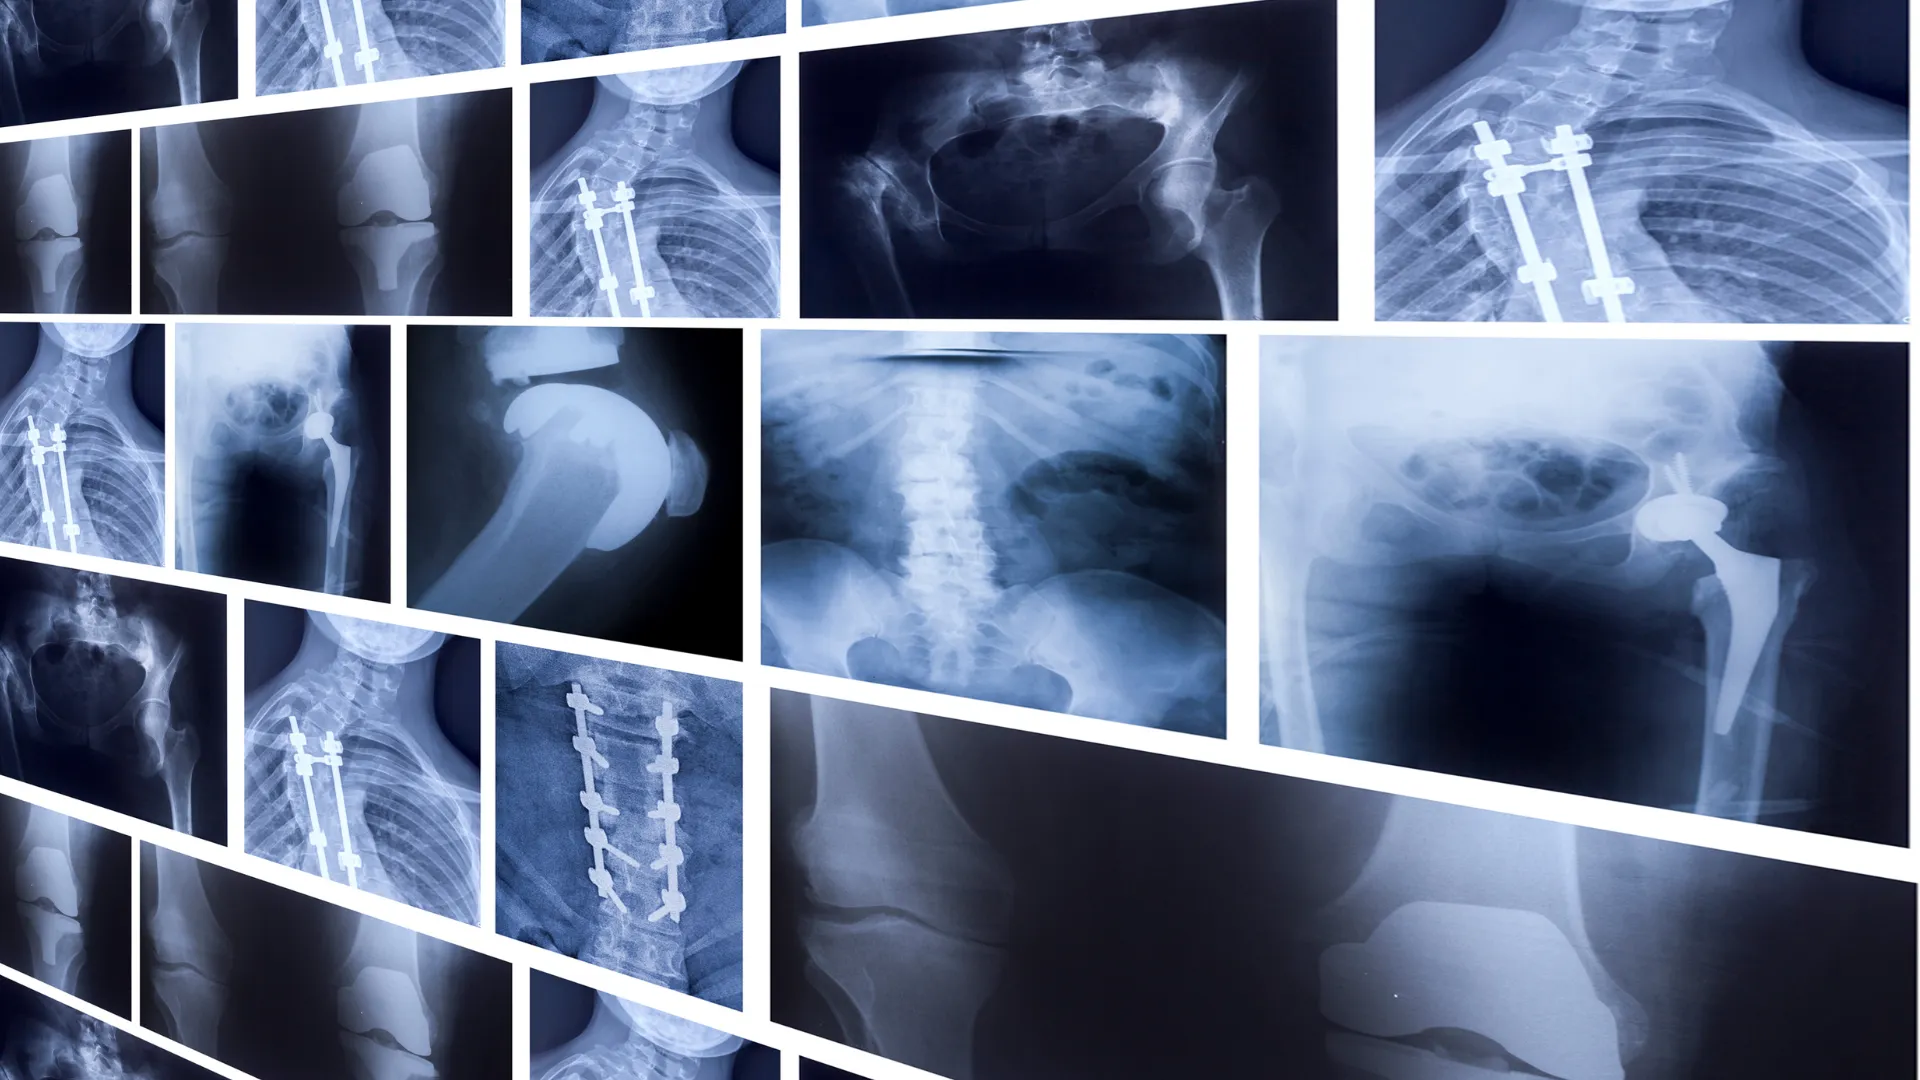

radiografías de diferentes parte del cuerpo

En el servicio de radiología, se capturan imágenes precisas del interior del cuerpo mediante equipos de alta tecnología para identificar anomalías estructurales. Estas imágenes son hoy en día fundamentales para la detección precoz de enfermedades, la planificación del tratamiento y la monitorización de su respuesta. Los radiólogos utilizan también los aparatos para tratar enfermedades y lesiones de las personas atendidas.

• Radiología convencional: aparatos que utilizan rayos X para obtener radiografías bidimensionales de las estructuras internas del cuerpo, permitiendo diagnosticar fracturas y neumonías, entre otros.